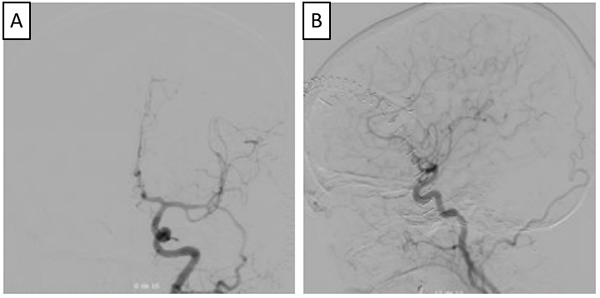

Figura 1. RMN de cráneo en la que se identifica lesión sacular de localización supraselar con efecto de masa, mide 22 mm x 19 mm x 17 mm (A), desplaza y comprime el quiasma óptico y la porción cisternal de ambos nervios ópticos, especialmente el del lado derecho (B), tiene un área en forma de media luna que realza tras la administración del medio de contraste (B y C). En la parte inferior se observa la Arteriografía cerebral con un aneurisma sacular de contornos irregulares, localizado en el segmento comunicante anterior de 8mm x 6mm x 5 mm (D, E y F).

Para definir con mayor detalle la anatomía vascular, se realizó una arteriografía (Ver Imagen 1), con la que se confirmó la presencia de un aneurisma sacular de la arteria comunicante anterior, de contornos irregulares, de 8x6x5 mm, sin signos de ruptura con una orientación antero-inferior. Esta clara diferencia entre el tamaño de la lesión en la RNM y la arteriografía confirma la presencia de un trombo intra-aneurismal.